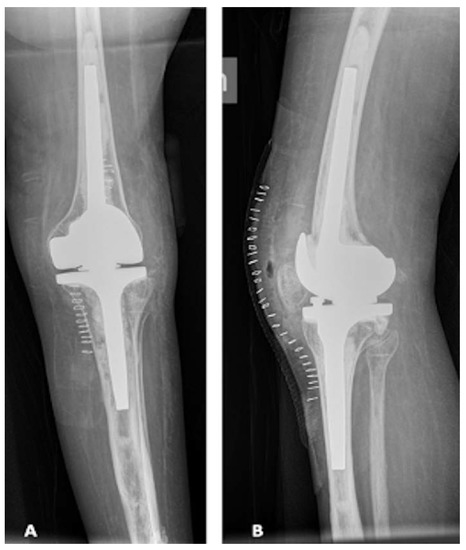

With these data on both bone morphology, bone loss and bone thickness, a careful surgery simulation was performed, including size of cone (used both to fill tibial bone loss and to achieve a good fixation in the metaphysis) and zones of safe position, without damaging femoral or tibial cortex, as well as size of the chosen implant (Endomodel®, Waldemar Link GmbH, Hamburg, Germany). Figure 10 shows X-rays one year after surgery, with good implant fixation, no signs of loosening in a satisfied patient.

Figure 10. X-rays one year after surgery. (A) Long-leg weight bearing view; (B) lateral view; (C) antero-posterior view, (D) patellar view.